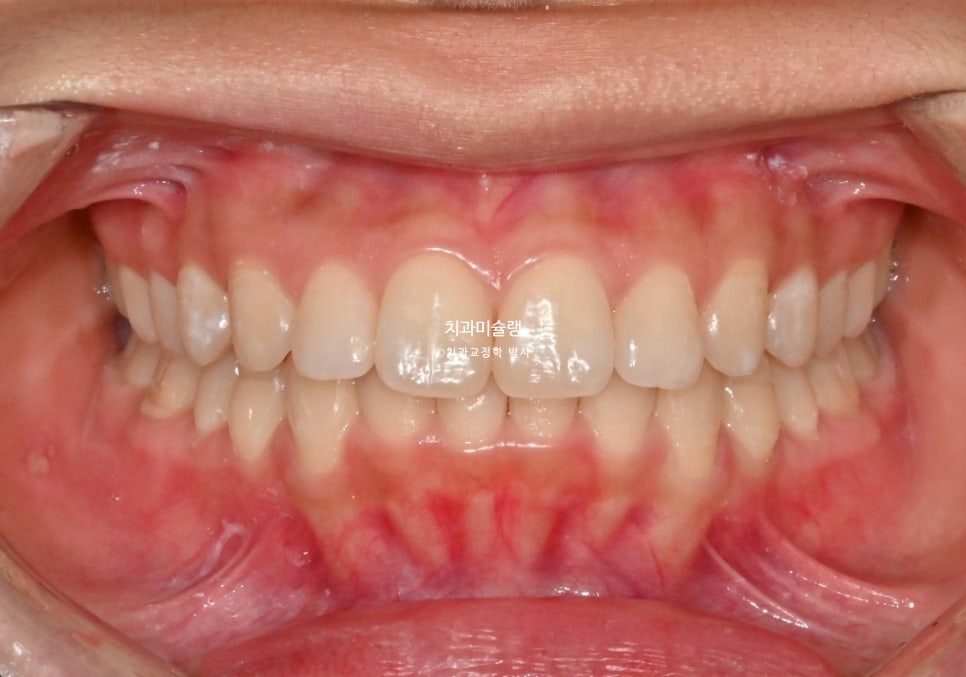

중심선 불일치와 과개교합이 보입니다.

중심선은 정확히 맞으며 과개교합은 개선되었습니다.

어금니 교합관계는 1급관계를 달성.